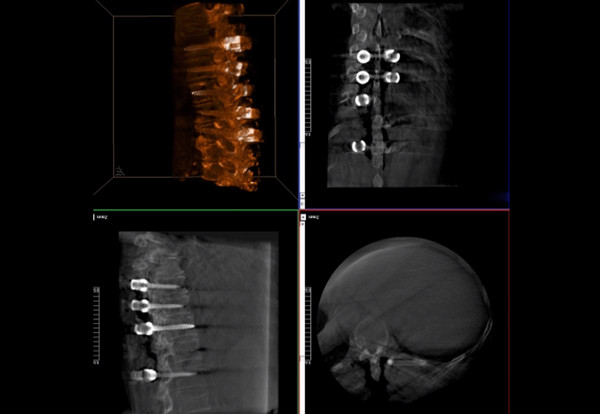

普愛醫療術中三維導航C臂快速生成橫斷面、矢狀面、冠狀面斷層圖像和三維立體圖像,方便醫生確認手術部位。C形臂的大平板帶來出色的顯示視野,可以更好的顯示手術部位全局情況,確保手術規劃及執行的準確性。

術中三維導航C臂影像

三維影像檢驗螺釘植入效果